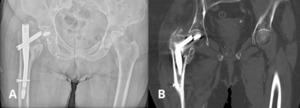

An 87 year old female patient with a history of arterial hypertension and early-stage dementia presented at the emergency department after a fall from standing height. Plain radiographs demonstrated a subcapital fracture of the right femur accompanied by a fracture of the cephalic lag screw of a previously implanted intramedullary nail. The nail itself was still in the same position, and no signs of loosening or failure at the original fracture site were identified. Following this, a computed tomography (CT) scan was made to evaluate the condition of the previous intertrochanteric fracture and confirmed no evidence of fracture non-union, malalignment, or any other structural abnormalities. Figure 1 shows the anteroposterior X-ray and CT scan of the subcapital femoral neck fracture and fractured cephalic lag screw.

_anteroposterior_x-ray_demonstrating_the_subcapital_femoral_neck_fracture_and_a_fractur.png)